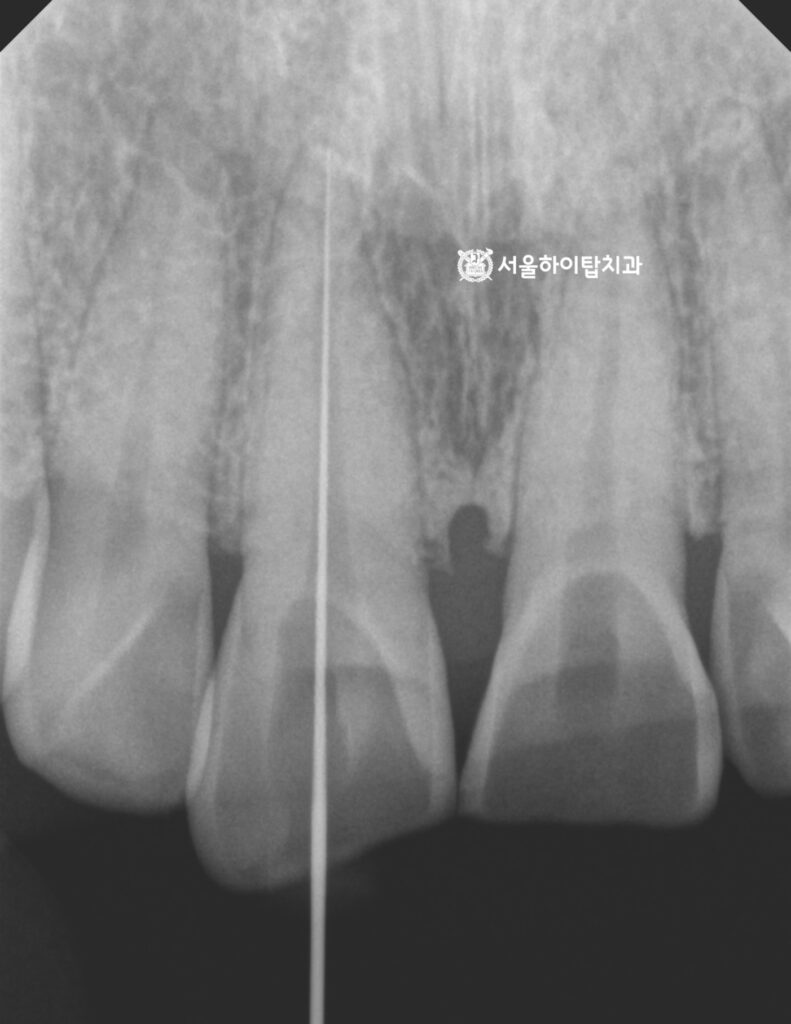

계획 수립 – 신경치료 및 보철 수복

현재 교모의 정도가 매우 심하고,

치아 형태와 길이가 많이 소실된 상태입니다.

특히 마모가 깊게 진행되면서

치수와의 거리가 매우 가까워졌거나,

이미 외부 자극에 민감한 증상이 동반되는 양상을 보이기 때문에

추가적인 파절이나 교모가 발생하기 전에

신경치료와 보철 수복을 통해 장기적인 안정성을 도모하고,

전체 교합 밸런스를 재정립하는 치료가 필요할 것으로 판단됩니다.

또한 부평 치과 에서는 치관 길이가 짧은 경우

보철적 유지력을 확보하기 위해 치관 높이를 확보한 뒤

지르코니아 크라운 제작을 진행할 수 있다고 설명드립니다.